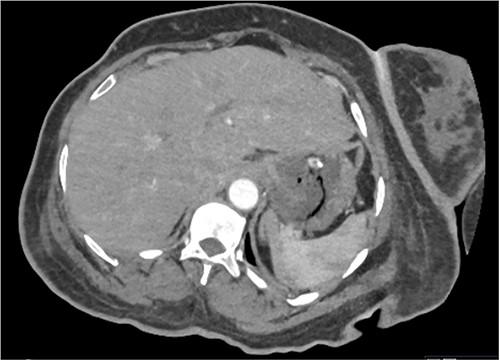

Whilst awaiting her planned orthopaedic surgery, the patient developed epigastric and retrosternal chest pain on Day 13 of admission, associated with persistent vomiting and abdominal distension. On examination, she had a moderately distended abdomen, with no focal peritonism present. Initial blood tests performed showed mildly elevated inflammatory markers, normal serum troponin levels, and a raised D-dimer. As such, a computed tomography (CT) pulmonary angiogram was initially performed; whilst no evidence of pulmonary embolism was identified, an incidental finding of gas within the liver peripheries (Fig. 1A) and the gastric fundal wall was noted (Fig. 1B). A subsequent plain film abdominal radiograph performed showed a significantly distended stomach (Fig. 2).

CT pulmonary angiogram images demonstrating moderate amount of branching linear gas in the liver (long arrows), most pronounced in (A) at the level of T11/12; gas within the wall of the gastric fundus (short arrows) can be appreciated more in (B) at the level of T11.